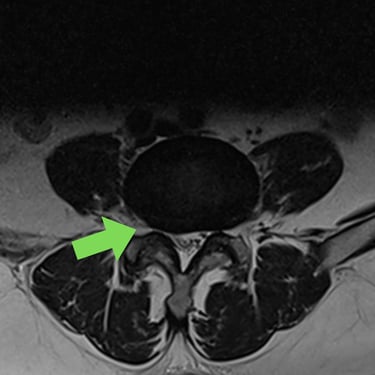

Listesis Lumbar: Artrodesis con Tornillos Transpediculares y Fusión Intersomática Transforaminal (TLIF).

La listesis lumbar es el deslizamiento anormal de una vértebra sobre otra, lo que puede generar dolor lumbar crónico, inestabilidad y compresión de las raíces nerviosas. Cuando el tratamiento conservador no es suficiente, la artrodesis con tornillos transpediculares (FTP) asociada a la fusión intersomática transforaminal (TLIF) es una técnica quirúrgica efectiva. Este procedimiento permite estabilizar la columna, restaurar la alineación vertebral y lograr una fusión sólida, al mismo tiempo que descomprime las estructuras nerviosas. La combinación de estas técnicas mejora el control del dolor, la función neurológica y la calidad de vida del paciente.